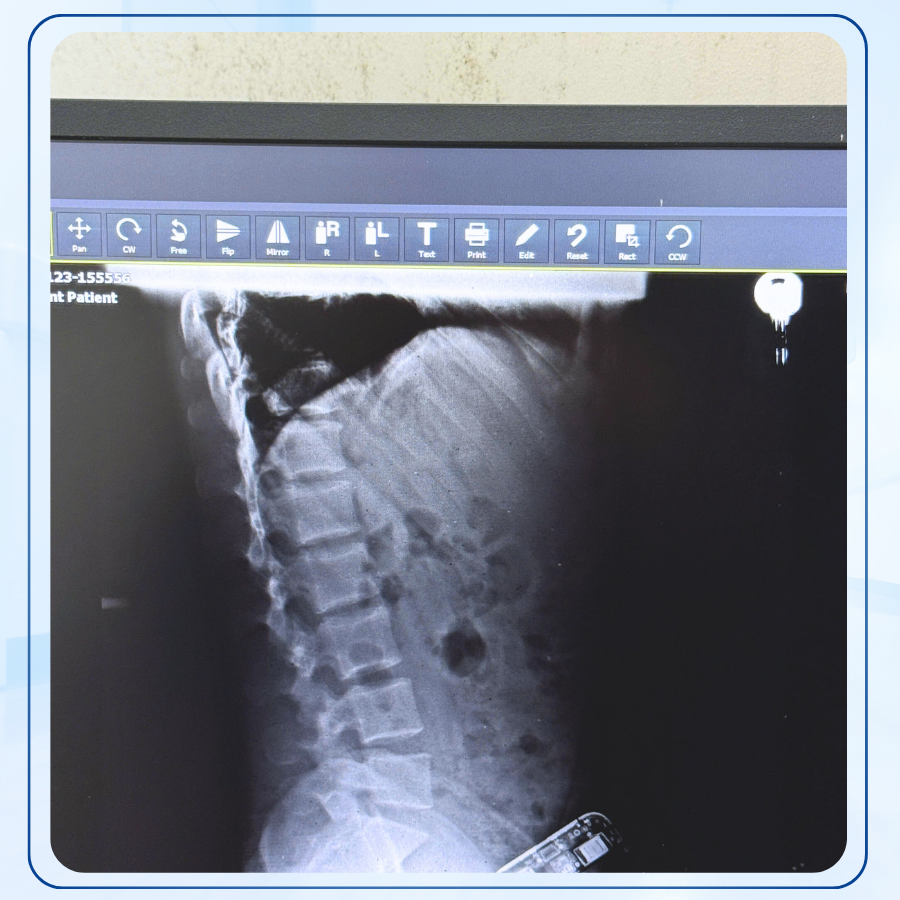

1.2. Nâng cao chất lượng hình ảnh

Hình ảnh X-quang bị sai lệch do:

- Hệ thống DR/CR hoạt động kém

- Bàn khám và giá chụp không ổn định

- Hỏng bóng X-quang, biến áp cao thế

- Cảm biến DR bị lỗi hoặc giảm độ nhạy

Bảo dưỡng giúp tối ưu hóa các thông số, làm sạch phụ kiện, hiệu chuẩn hệ thống, qua đó tăng độ nét – độ tương phản, hỗ trợ bác sĩ chẩn đoán chính xác hơn.